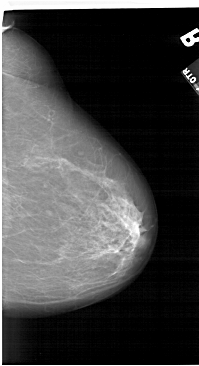

A_1124_1.LEFT_MLO

LEFT_MLO LINES 6196 PIXELS_PER_LINE 3616 BITS_PER_PIXEL 12 RESOLUTION 43.5 OVERLAY